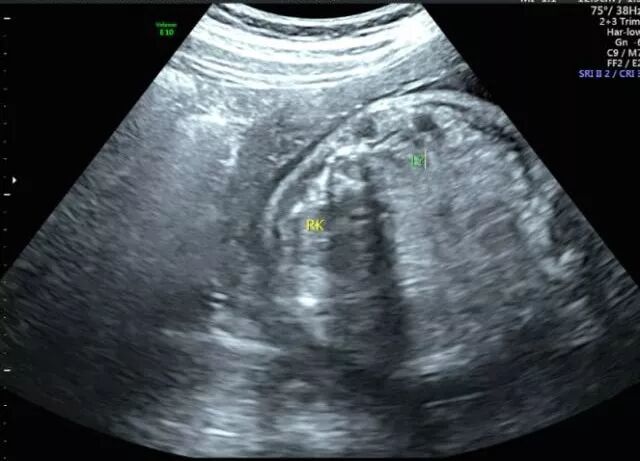

27岁的小美(化名)和相爱多年的男友结婚一年后,一个小生命的悄然到来,给整个大家庭送上了一份惊喜,他们俩感觉太幸福了。然而不幸的事情发生了:小美孕25周四维彩超检查发现胎儿下肢无双腿,双下肢合并外形似鱼尾状,据医生了解,这是一种非常罕见的多发性畸形,双下肢合并外形似鱼尾状,俗称“美人鱼综合症”。

无独有偶,一位40岁的二胎妈妈在一次常规的产检中,发现胎儿下肢是两个大腿骨, 并行排列 ,小腿骨好像有点交叉 。医生介绍正常胎儿的下肢是不停地在妈妈肚子里动的, 呈现一个外八字,像这种情况,医生从医40年也是第一次见,后来确诊为美人鱼综合症。因为多数患病的新生儿出生后,只能存活几个小时,就算活下来,也要接受多次手术治疗。最终,在医院的帮助下,这位二胎妈妈选择了终止妊娠。

(左肾缺如)